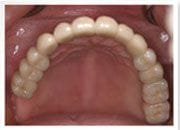

上顎植牙假牙完成, 恢復美觀及咀嚼功能

林小姐從無法咀嚼, 不敢開口, 植牙後可以自信的開懷大笑, 大口吃東西, 宛如重獲新生